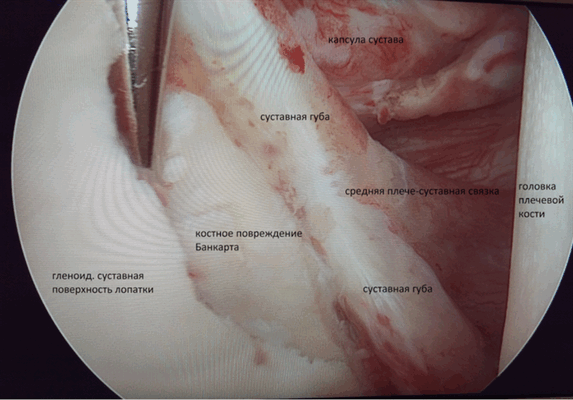

- Нестабильное состояние плечевого сустава(повреждение Банкарта, вывих плеча, в том числе и первичный)

А) При переднем вывихе ПС вмешательство направлено на восстановление суставной губы (операция Банкарта). Метод нацелен на восстановление целостности суставной губы при помощи фиксации оторванной части на край суставного отростка лопатки.

В) В случае сочетания заднего повреждения Банкарта, сопровождающегося задним разрывом связки суставной впадины лопатки, артроскопия позволяет зафиксировать оторванную суставную губу к краю суставной впадины лопатки, заднюю часть капсулы плеча к задней части головки плеча. В качестве фиксатора используются биорассасывающие фиксаторы-якоря.